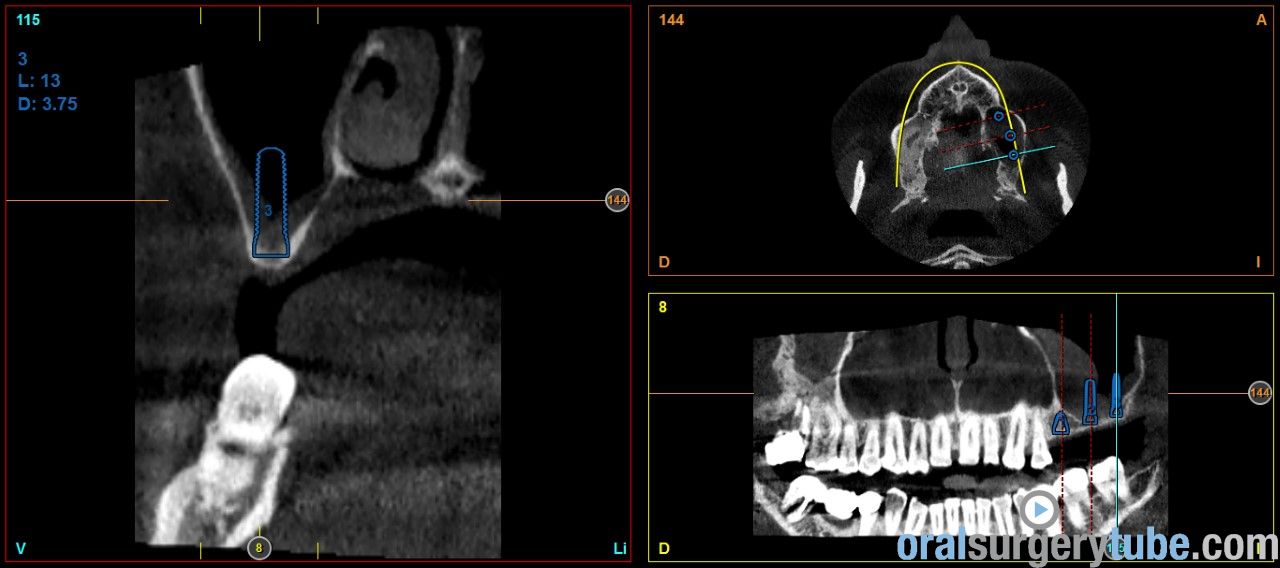

Engrosamiento mucoso

Estimados compañeros, me gustaria saber como abordaríais el seno izquierdo el cual como veis presenta engrosamiento mucoso. Haríais tratamiento previo? Gracias de antemano

Que opináis de dar un corticoide vía oral? Como la dexametasona?. Por cierto repetí el tac después de hacer la elevación derecha y de dar antibiótico y la verdad que el engrosamiento del sebo izquierdo a cambiado más bien poco por no decir que incluso se ha engrosado un poco más, pero eso sí, el paciente no refiere haber tenido en toda su vida síntomas de sinusitis ni alergia, imagino que la causa es la desviación que se ve del tabique hacia la izquierda y la concha bullosa del cornete medio, de verdad no se q hacer, si abordar el seno así ( ya que el paciente no tiene síntomas ) o derivarlo a un otorrino.Tampoco me parece exagerado el engrosamiento, qué opináis?

Hola a todos. Al hilo de este post que he visto, os presento un caso que me ha llegado hace poco a la consulta. Os envío imagenes. Se aprecia engrosamiento de la membrana del seno maxilar izdo. Pensaba darle Trigon Depot 10 días antes de la cirugía y luego valorar. Como lo veis? Muchas gracias.